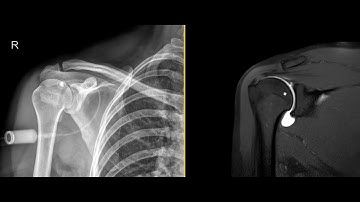

Shoulder CT Arthrogram: Protocol Guide for Radiology Techs